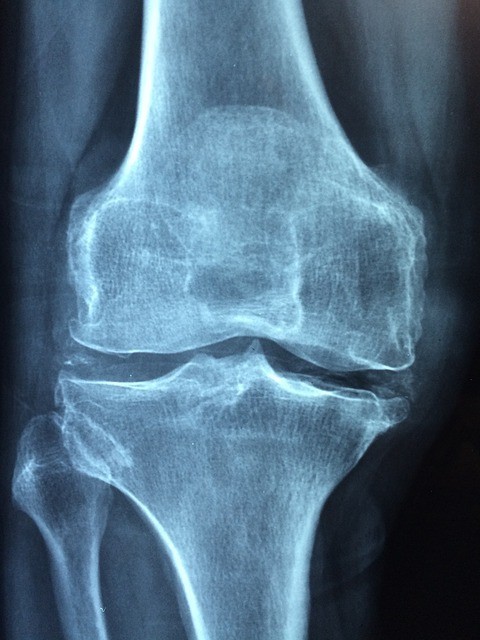

– Osteoarthritis:

In this case, the target is at the level of the cartilage which covers the articular surface and not at the level of the membrane. With age or following repeated micro-traumas as in sports, this cartilage can degenerate (wear trauma) and the bone is no longer protected against friction. The pain appears and movements become more difficult. We also talk about degenerative arthritis. It is more common after age 65 and represents the second leading cause of disability after cardiovascular disease. It is knee osteoarthritis (osteoarthritis of the knee) with digital osteoarthritis (fingers) and hip that are the most common.